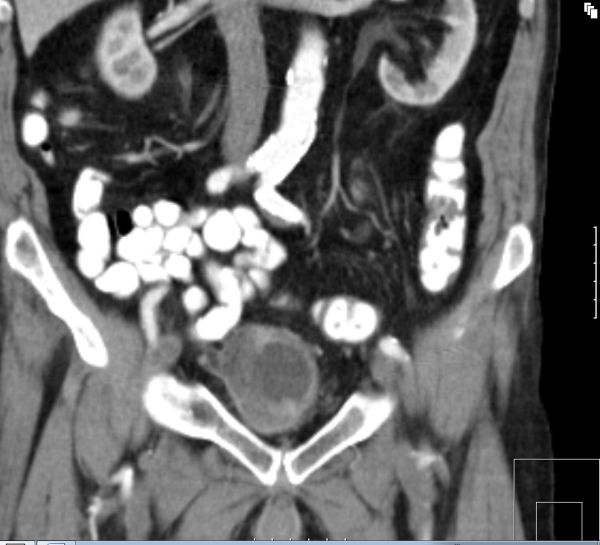

| T4-Tumor | 67-jährige demente Frau mit T4-Blasentumor

(invasives Urothelkarzinom) und Rektumkarzinom.![]() |

![]() |

![]() | |